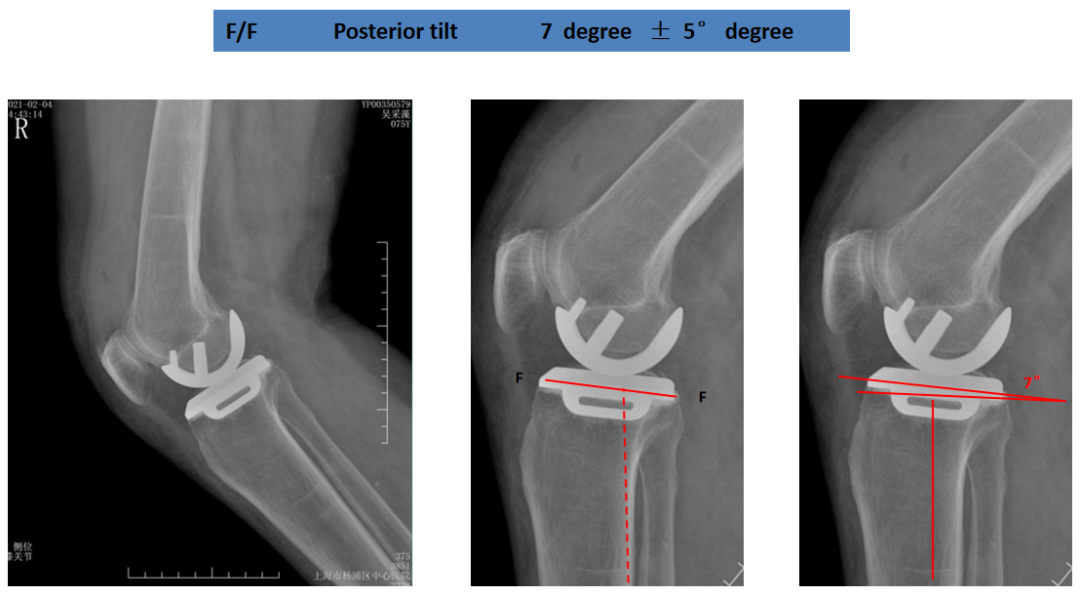

胫骨假体后倾角度(矢状位)

胫骨假体后倾角度:与胫骨侧位中轴线的垂线的最佳夹角 =7°。